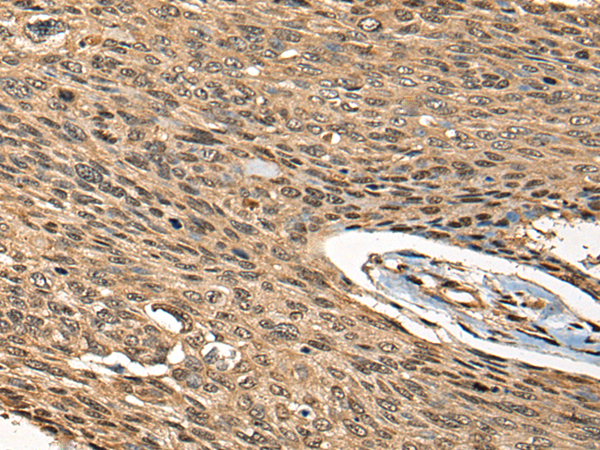

分类: 科研抗体货号: P09433别名: CPH应用: WB,IHC反应种属: Human, Mouse, Rat